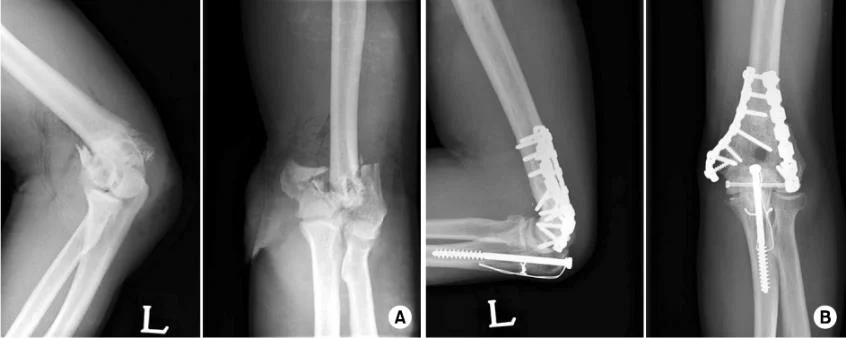

Fracture Distal Humerus

- Treated by open anatomical reduction and internal fixation by plates and screws

- Early mobilization to prevent elbow stiffness